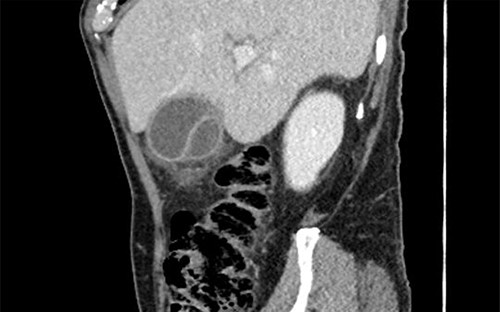

Subsequent review of preoperative imaging solved the mystery. Duplicated gallbladder with double cystic ducts was clearly evident on CT and magnetic resonance imaging (MRI) which were hidden in plain sight (Figs 4–7). CT cholangiogram (Fig. 3) was performed Day 1 post-operatively showing the double cystic duct with no evidence of bile leak. Rest of patient’s admission was uneventful and he was cleared for discharge on Day 5 post-operatively. Patient remains well and was back to his daily activities during his follow-up review.

Axial section of preoperative CT abdomen from initial presentation showing thickened gallbladder with pericholecystic fluid; duplicated gallbladder evident, initially thought to be Phrygian cap sign.